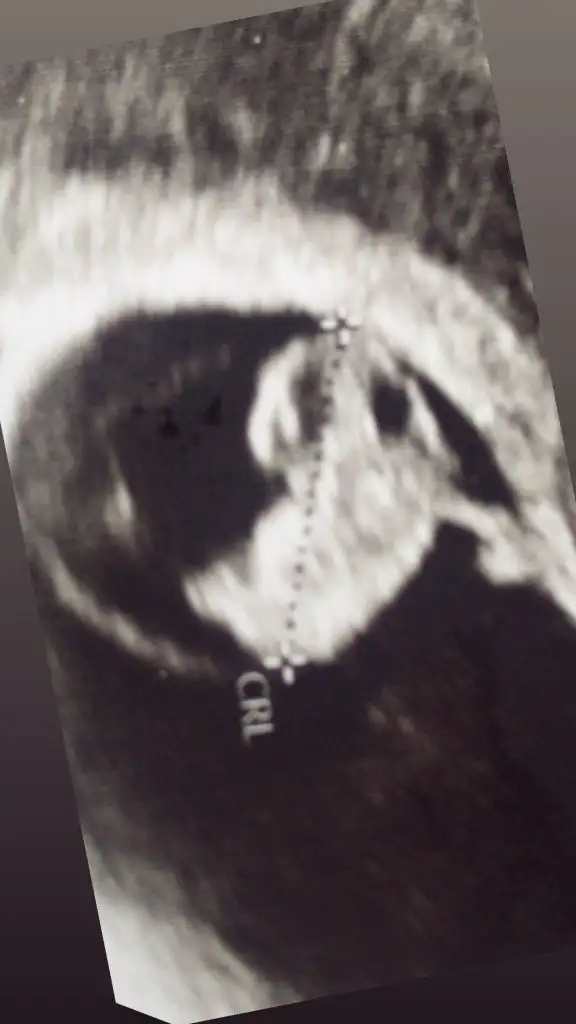

6-7-8 Haftalık bebeğin göründüğü bir ultrasonu gösterirsen yorumlarım ama uzaktan olsun kağıdın neresi düz görünsün ve vajinal mı karından mi olduğunuda belirt

6-7-8 Haftalık bebeğin göründüğü bir ultrasonu gösterirsen yorumlarım ama uzaktan olsun kağıdın neresi düz görünsün ve vajinal mı karından mi olduğunuda belir

• 1A9C52DE-1E94-451A-A8DF-1446F344430F.webp

19,8 KB · Görüntüleme: 120